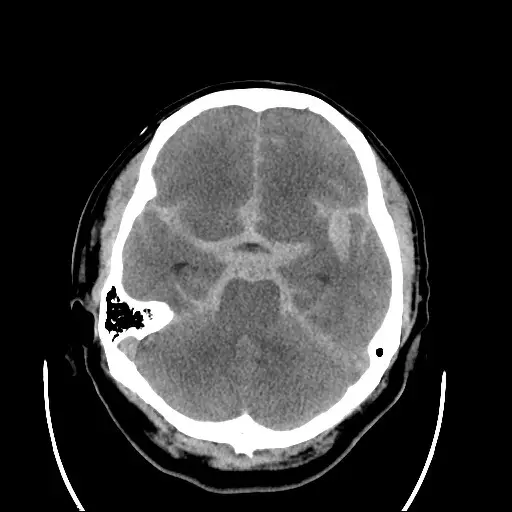

本題附圖與上題相同,為同一患者的腦部非顯影電腦斷層(non-contrast CT of brain):

- 高密度出血灶:左側顳葉內側/Sylvian 裂區域有明顯高密度(白色)不規則出血,形狀不規整,提示急性血液積聚(SAH 或顱內血腫)。

- 出血位置意義:Sylvian 裂(外側裂)及顳葉底部的出血,與後交通動脈(PCoA)走行及動脈瘤好發位置相符。後交通動脈瘤位於頸內動脈末端與 PCoA 交界,破裂時血液易積聚於 Sylvian 裂、鞍上池(suprasellar cistern)、環池(ambient cistern)等部位。

- 腦室及中線:腦室形態正常,中線未見明顯偏移,暫無急性腦疝徵象。

影像與診斷的關聯:CT 所見高密度出血合併臨床表現(突發頭痛 + 動眼神經麻痺),支持後交